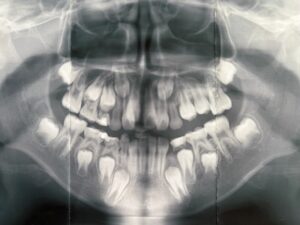

例えば、9歳男子

顎の細いシュッとしたお顔の9歳男子。大人の歯がキレイに並ぶには、顎が小さいです。顎の成長にも不安が見られるため、矯正専門医に紹介させていただきました。第二次性徴も考えますと、大学卒業頃までは、観察が必要と思います。